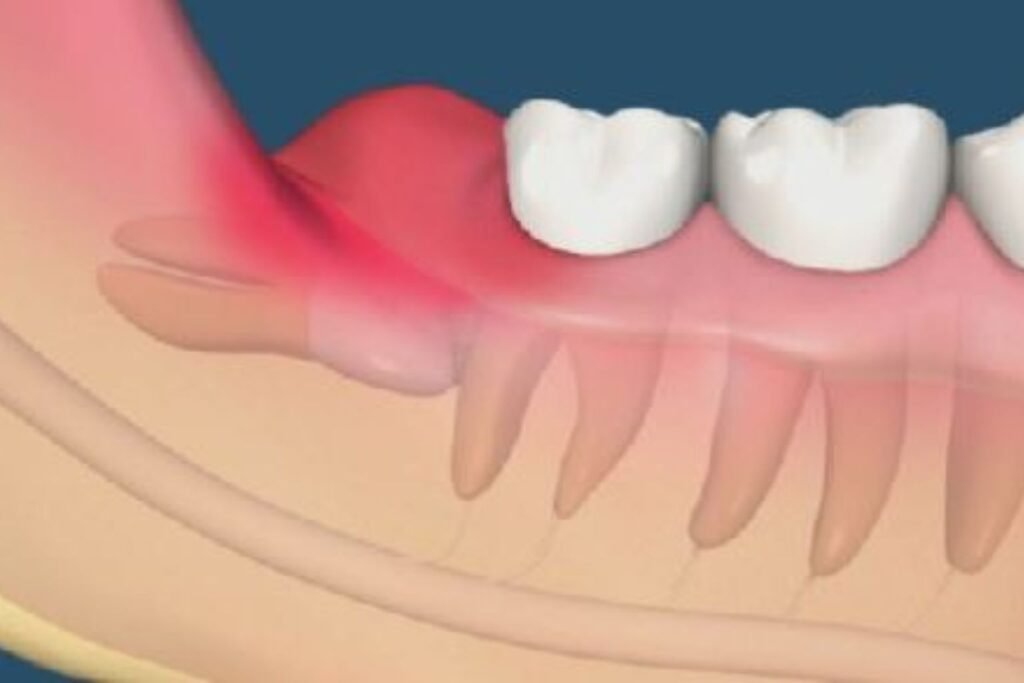

2. Inflamação e Infecção Recorrente (Pericoronarite)

A pericoronarite é uma inflamação da gengiva ao redor de um dente do siso que está parcialmente erupcionado. Este é um dos sinais mais claros de que você precisa extrair o siso, pois indica que o dente não tem condições de nascer completamente e está criando um ambiente propício para infecções.

Sintomas da Pericoronarite

Quando você desenvolve pericoronarite, pode experimentar:

- Inchaço na gengiva: A região ao redor do siso fica visivelmente inchada e avermelhada

- Dor intensa: A dor pode ser tão forte que dificulta abrir a boca ou mastigar

- Mau hálito persistente: A infecção causa um odor desagradável que não melhora com escovação

- Sabor ruim na boca: Você pode sentir um gosto desagradável, resultado da infecção

- Dificuldade para engolir: Em casos mais graves, o inchaço pode afetar a deglutição

- Febre: Infecções mais severas podem causar febre e mal-estar geral

Por Que É Grave

A pericoronarite acontece porque, quando o dente do siso está parcialmente coberto pela gengiva, forma-se uma “bolsa” entre o dente e o tecido gengival. Essa bolsa é um local perfeito para o acúmulo de restos de alimentos e bactérias, que são praticamente impossíveis de limpar com escovação normal. As bactérias se multiplicam, causando infecção que pode se espalhar para outras áreas.

O mais preocupante é que a pericoronarite tende a ser recorrente. Você pode tratar a infecção com antibióticos e anti-inflamatórios, mas se o dente continuar parcialmente erupcionado, a infecção voltará. Cada episódio de pericoronarite aumenta o risco de complicações mais sérias.

Quando Extrair

Se você já teve dois ou mais episódios de pericoronarite, este é um sinal claro de que você precisa extrair o siso. A extração é a única solução definitiva para prevenir novos episódios de infecção e proteger sua saúde bucal.